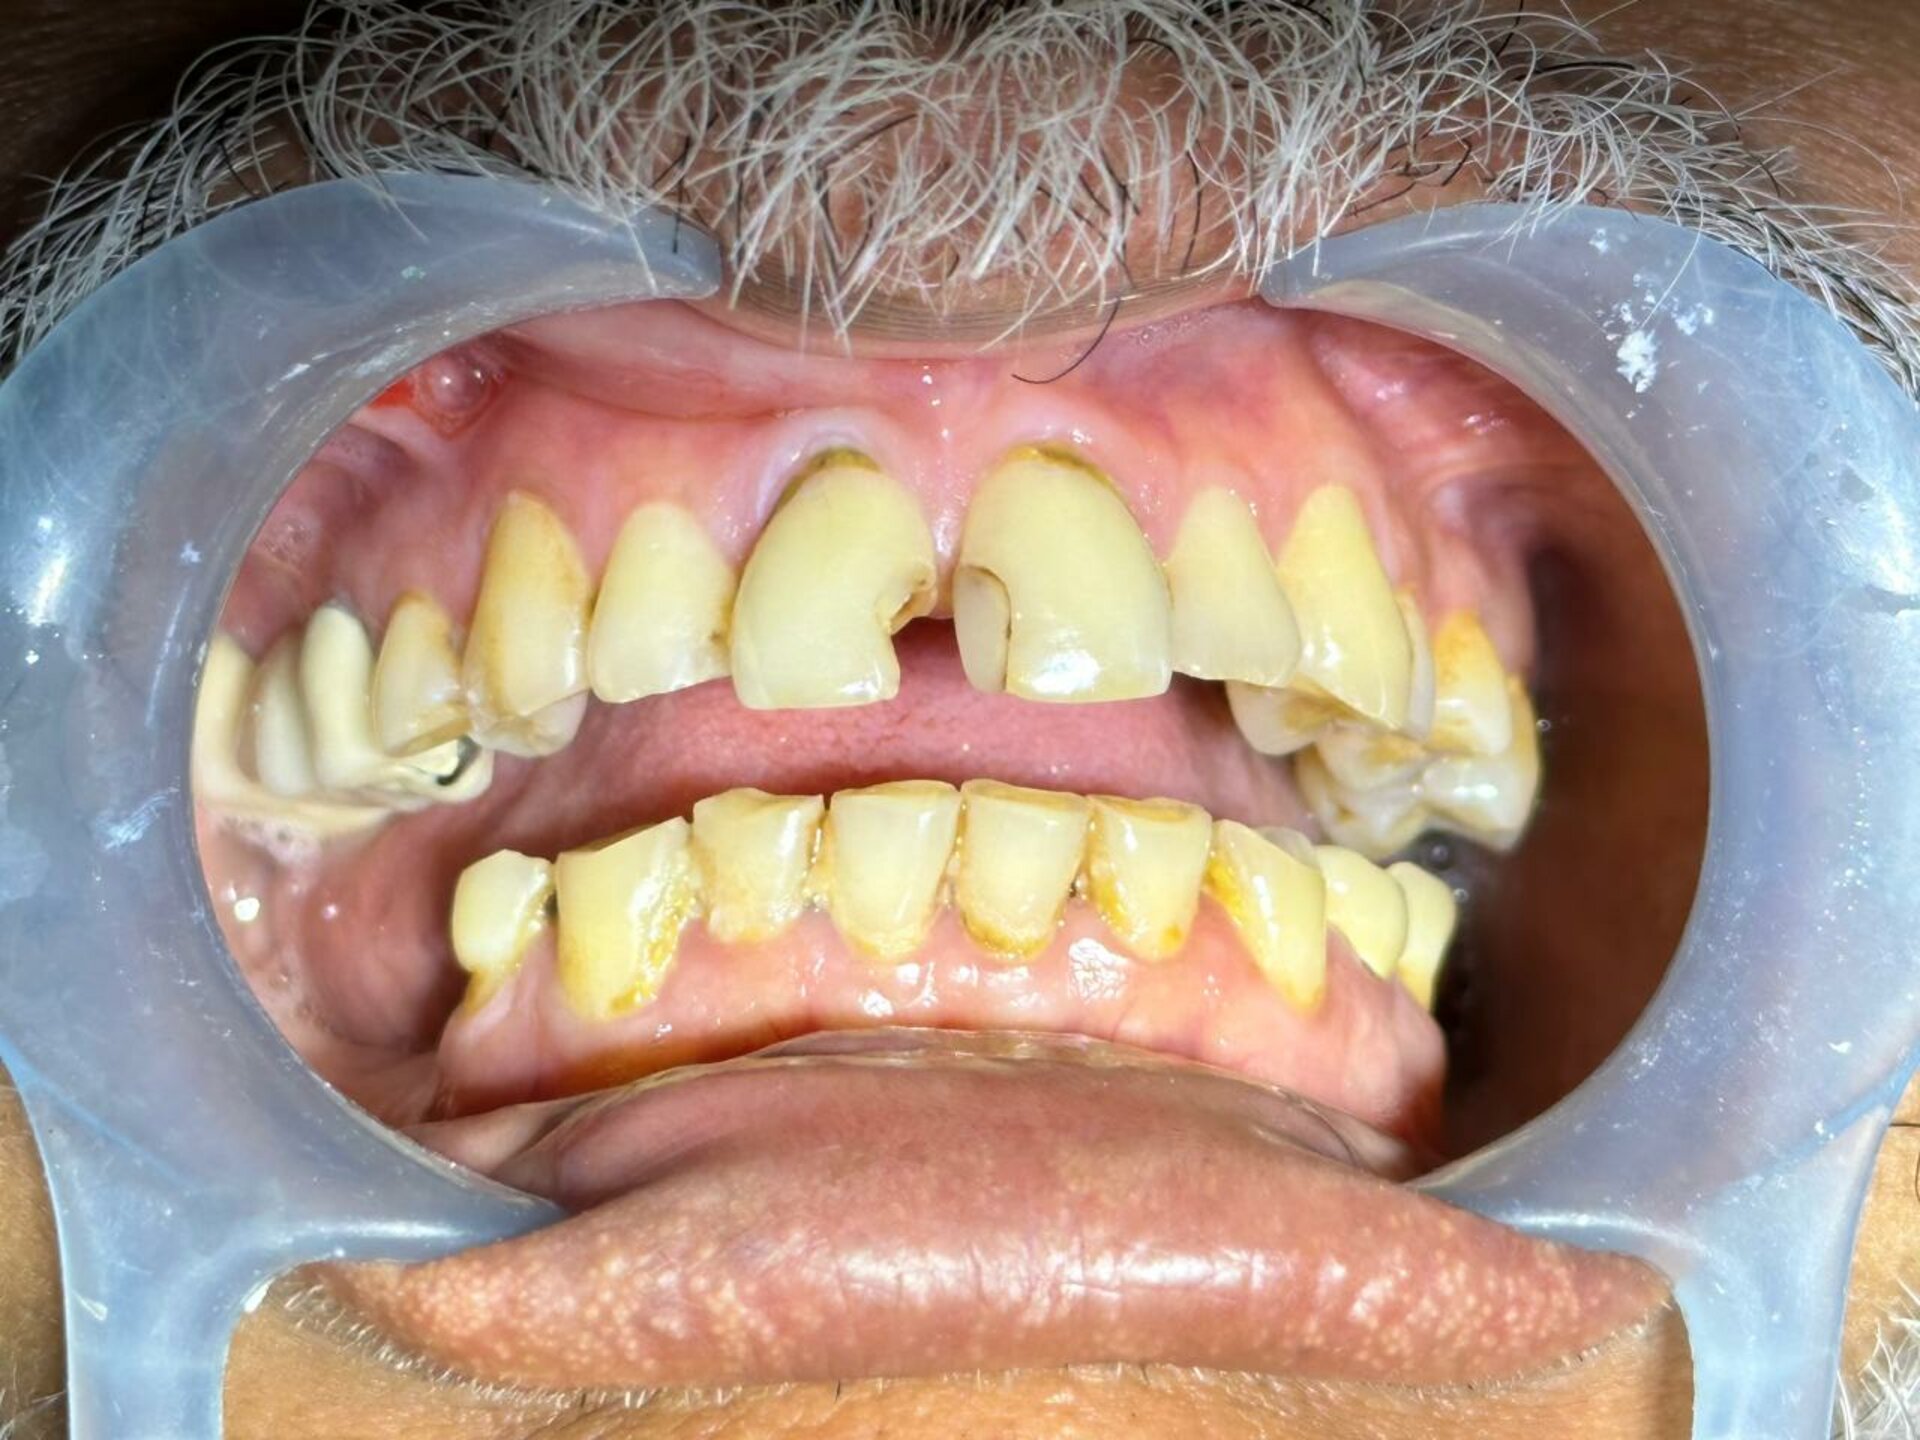

Dr. Gautami Phadke, Consultant Dental Surgeon and Root Canal Specialist in Karve Nagar, Pune, recently transformed the smile of a 60-year-old patient ...